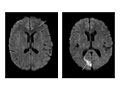

Tumors in the brain or in areas outside the brain, such as an acoustic neuroma, are present.

Bleeding or swelling (edema) in or around the brain is present.

Areas of infection or inflammatory disease, such as encephalitis or meningitis, are present.

Abnormal areas in the brain may mean that certain diseases, such as Huntington's disease, multiple sclerosis, Parkinson's disease, or Alzheimer's disease, are present.

Bulges or weak areas (aneurysms) or abnormal blood vessels (such as an AV malformation) are present.